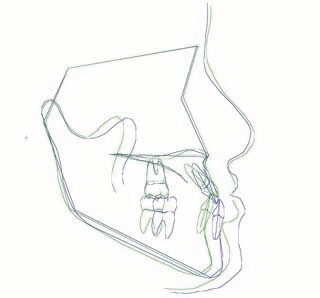

外科症例(アゴの輪郭でお悩みの方) 下顎前突

装置撤去です。動的処置は2年弱でしたので、通常のマルチブラケット治療とそれほど治療期間は変わりません。しかしながら、わずかな正中のズレが残ってしまいました。大きくは改善したのですが、左右のズレというものは、比較的、後戻りが現れやすい問題です。筋肉の影響によるものや、咬合平面の傾斜が左右的に水平でない事などが関係しているような気がします。今後は保定治療に移行し、数年にわたって咬合の安定状態を管理していきます。